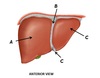

Name structures A and B

A - Falciform ligament

B - Greater omentum